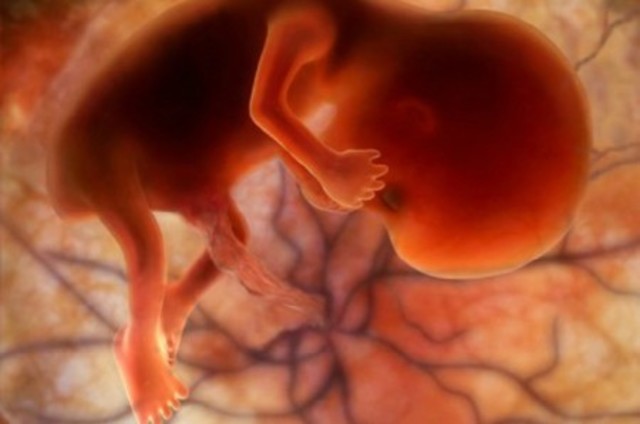

SEMANA 7

Alrededor de esta semana, el embrión se convierte en feto, en esta fase, los tejidos y órganos formados durante el periodo embrionario comienzan a madurar, el esqueleto comienza a tomar forma, al igual que el cordón umbilical comienza a ensancharse.